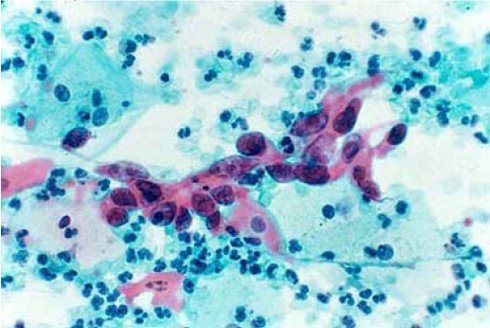

Mikroskopisches Bild veränderter Schleimhautzellen des Gebärmutterhalses

Quelle:

Deutsches Krebsforschungszentrum Heidelberg, Forschungsschwerpunkt: Infektionen und Krebs, Prof. Dr. Gissmann